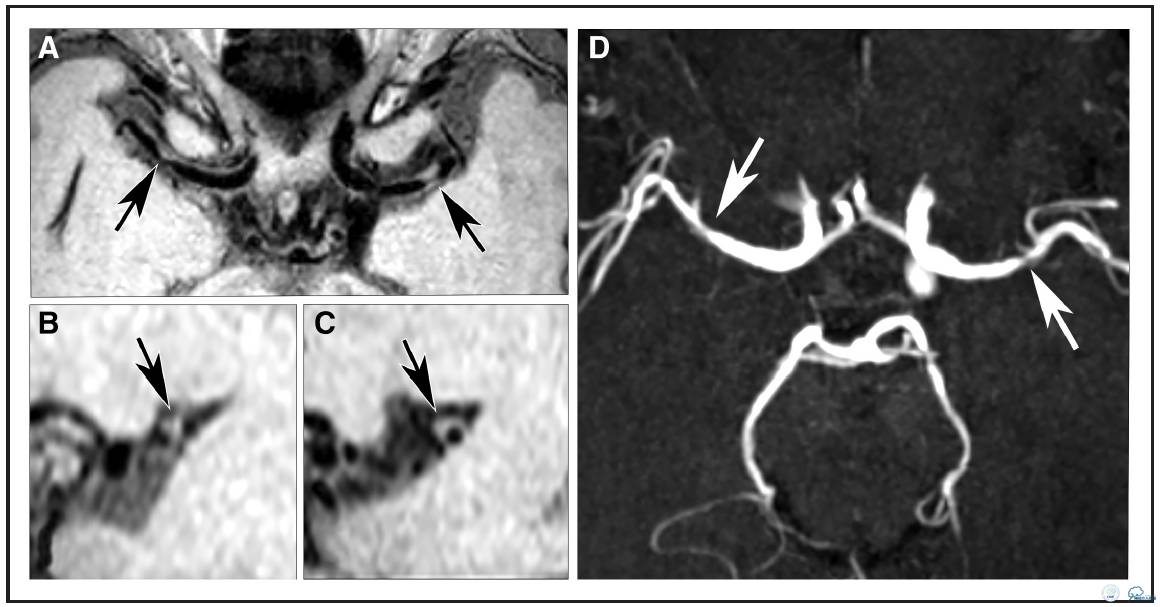

分布、负荷和特征

18例患者(95%)存在颅内血管壁病变,15例患者存在多发病变。评估者间信度很高:组内相关系数为0.71,95%置信区间(0.196-0.920)。评价位置的评估一致性中等偏上,Dice相似系数Dice为0.57。494处受检节段中总共发现57处病变(12%),其中47处(82%)位于前循环(颈内动脉[ICA],n = 18;大脑中动脉[MCA],n = 27,大脑前动脉[ACA], n = 2),10处(18%)位于后循环(基底动脉[BA],n = 3 ;大脑后动脉[PCA],n = 7,见表2及图1)。57处病变中,25处(44%)注射造影后有强化(图2),43处(75%)为偏心性病变,14处(25%)为向心性病变,42处(74%)为局部增厚,15处(26%)为弥散增厚(表3)。在前循环斑块中,偏心病变同局部增厚存相关(图2,图I在线数据补充),向心病变同弥漫性增厚相关(P< 0.001)。19处病变(33%)为症状性病变(MCA病变;1例患者双侧病变),38处病变(67%)为无症状性病变。比较无症状和症状性病变时, 发现偏心性病变和无症状病间存在很大的相关性(P< 0.05)(无症状病变中有32处为偏心病变,占84%;症状性病变中有11处为偏心病变,占58%),但与强化或特定的增厚型式无关。症状性病变没有任何特定的形态特性。此外,MRA上显示正常或不规则的血管壁病变常为无症状病变,而MRA上显示狭窄的或闭塞病变是为症状性病变(P < 0.001;图2)。MRA显示的30处病变中:26处位于前循环,4处位于后循环。此外,MRA上显示的8处病变是在血管壁扫描序列上发现相应病灶。这些病变中,6处为不规则病灶,1处是狭窄病灶(图3),另1处为不规则且闭塞病灶。两处狭窄病灶同时也是症状性病灶。

图3:64岁男性患者,左侧大脑中动脉(MCA)狭窄引起的左侧部分前循环梗死。A:TOF-MRA示左侧大脑中动脉(MCA)存在小的狭窄(白箭头)。B:横向的T1加权自旋回波采集容积重建图像上没有相应的血管壁病变。